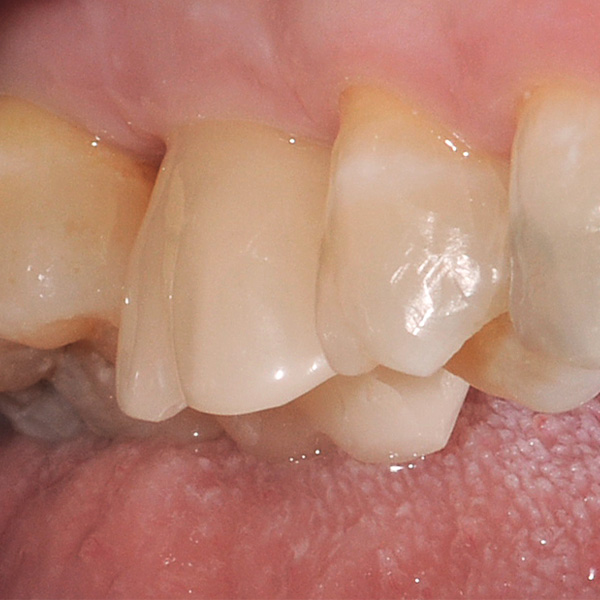

Restorations and implants are exposed to especially high loads. After extraction and implantation, the patient lacks the elastic fiber apparatus of the natural dental bed. As a result, chewing forces are not absorbed, but transmitted directly to the restoration, the implant, the bone and the opposing dentition. The hybrid ceramic VITA ENAMIC provides a dual network structure of ceramic (86 wt%) and polymer (14 wt%). This results in a dentin-like elasticity and the ability to absorb chewing forces. Due to its high vertical dimension, the polychrome blank VITA ENAMIC multiColor in the EMC-16 geometry enables the production of one-piece, monolithic abutment crowns, even with atrophied bone. In the following article, dentist Professor Dr. Alexander Hassel demonstrates how he provides a patient with this type of restoration.